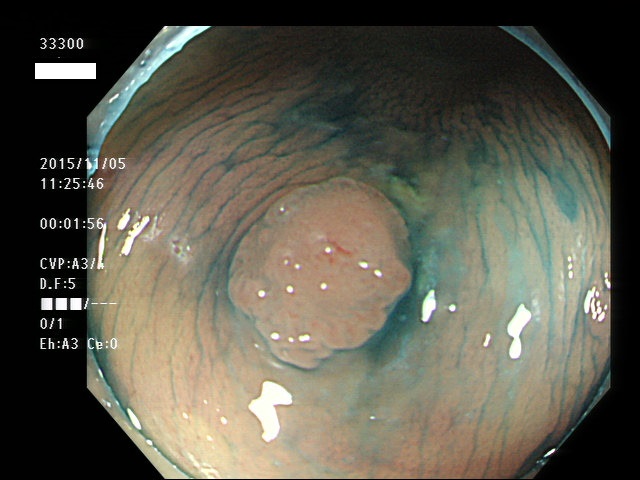

上記100名より抽出した平坦・陥凹型腺腫(=癌化の危険が高いが見落としやすい病変)の内視鏡写真